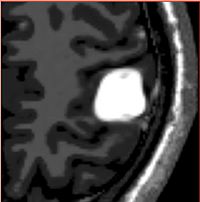

Segmentation TBI u.png

Analysis of Brain Images with Pathological Changes

Ongoing: Quantification, analysis and display of brain pathology as observed in MRI is important for diagnosis, monitoring of disease progression, improved understanding of pathological processes and for studying treatment strategies. We conduct research on developing novel methodologies that covers registration, segmentation, visualization of pathological structures with the aim of quantifying changes due to lesions, bleeding, and deformations over time. More...

Bo Wang, Wei Liu, Marcel Prastawa, Andrei Irimia, Paul M. Vespa, John D. Van Horn, P. Thomas Fletcher, and Guido Gerig . 4D Active Cut: An Interactive Tool for Pathological Anatomy Modeling, In Biomedical Imaging (ISBI), 2014 IEEE 11th International Symposium on, pp. 529-532. IEEE, 2014.